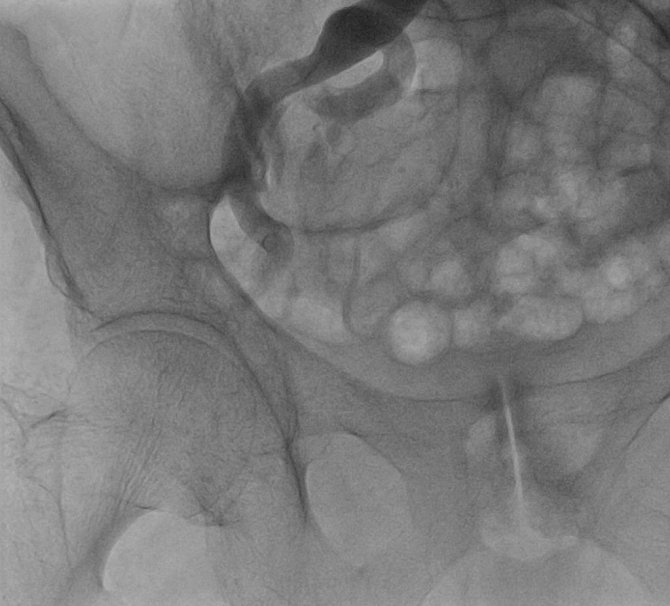

Sekiz yıl önce geçirdiği operasyonla aort kapak operasyonu değiştirilmiş bir hastaya TAVİ yöntemi ile müdahale ettiklerini söyleyen Doç. Dr. Servet Altay, "Hastamız 72 yaşında. 8 yıl önce aort kapağı biyolojik kapakla değiştiriliyor. Bu kapaklarında 10 yıllık bir ömürleri var. Hastamız bize geldiğinde ileri derecede nefes darlığı çekiyordu. Ayrıca aort kapağı değişen birinde ikinci operasyonun riski daha yüksek oluyor. Ekip olarak bu hastaya ne yapacağımızı düşündük. Daha önce bu bölgede yapılmayan bir işlemi yapmaya karar verdik. Türkiye'de de çok yaygın olduğunu düşünmüyoruz. Bozulmuş biyolojik kapağın yerine TAVİ dediğimiz yöntemle yeni bir kapak ekledik ve hastamızı sağlığına kavuşturmuş olduk. Bundan sonra da bu vakalara devam edeceğiz. Hasta günlük ihtiyaçlarını bile karşılamayacak durumdayken bu operasyonla kısa zamanda tamamen sağlığına kavuşmuş oldu. Açık bir ameliyat olmadığı için hastamız hiçbir şey hissetmedi. Yoğun bakımda da kısa bir yatıştan sonra direkt servise aldık. Bizim ve hasta için konforlu bir işlem oldu" dedi.

Yenilikçi bir yaklaşımla müdahalede bulundukları hastanın da benzer bir hikâyesi olduğunu söyleyen Dr. Öğr. Üyesi Uğur Özkan, "Hastamızın durumunu kliniğimizde ve konseyimizde değerlendirdik ve TAVİ kararı aldık. Hastaya işlemi gerçekleştirdikten sonra 24 saatten kısa bir süre yoğun bakım ve 48 saatten kısa servis yatışı oldu. Hasta açısından hem konforlu hem yoğun kan sulandırıcı kullanımı gerektirmeyen, günlük hayatına çok çabuk bir şekilde dönebileceği bir işlem oldu. Hastada çok çabuk ve güzel bir yanıt aldık. Üç gün önce nefes alamayan hastamız bugün yürüyerek servis içinde dolaşmaya başladı" şeklinde konuştu.